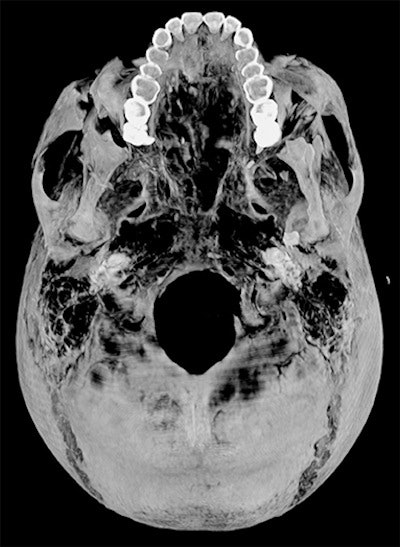

Saleem examined the mummy on 4 May 2019. She said she used the usual optimum CT scan parameters, including field-of-view and slice thickness, to provide the best 3D reconstruction. Because of the COVID-19 pandemic, it took several weeks to study the Hyksos weapons stored at the Cairo Egyptian Museum and to correlate them with the injuries by physical inspection of the mummy and on CT scans.

She has conducted CT scans for all the royal mummies housed at the Egyptian Museum in Cairo, using the CT machine located in the garden of the museum. She recently investigated 15 royal mummies that have not been scanned before with CT, including Seti II, Amenhotep II, Siptah, and Ramesses IV, V, VI, and IX.

Soon, the royal mummies will be transferred from the Egyptian Museum to the National Museum of Egyptian Civilization (NMEC), a new facility in Cairo. To avoid unnecessary transportation of the mummies, it was convenient to do the scans using the CT unit at the Egyptian Museum while they were still housed there.

"The results of the investigations helped in preparing the mummies to be transferred to the new museum. The Egyptian Ministry of Antiquities appointed me as a member of the NMEC's Display Scenario committee," Saleem told AuntMinnieEurope.com. "I used illustrated CT scan images to be displayed alongside some of the royal mummies in their new home. Digital illustrations will enhance the museum visitors' experience."